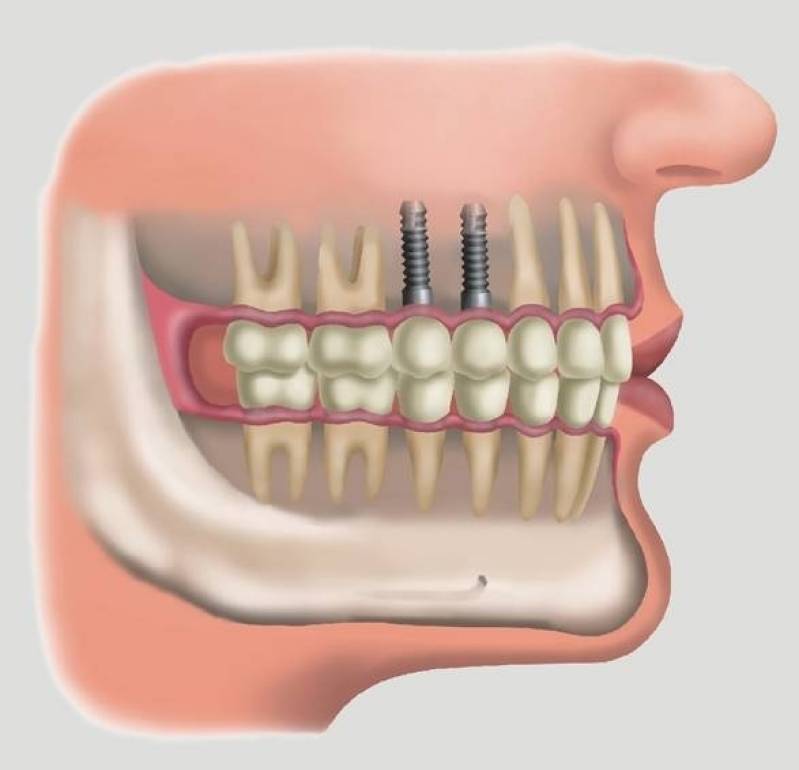

Implante dentário é formado por um cilindro (pino) de titânio, que é inserido dentro do osso, abaixo da gengiva. O tamanho do cilindro varia entre 3 e 6 mm de diâmetro. O titânio, metal biologicamente compatível que se integra perfeitamente ao osso, tem a peculiaridade de impedir qualquer tipo de rejeição óssea. Dessa forma, o implante dentário faz o papel da raiz do dente. Sobre os implantes é que são colocadas as próteses em metalocerâmica, que é o material mais semelhante ao dente natural.